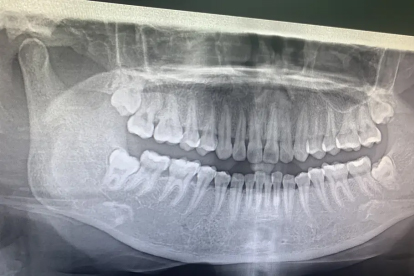

智齿牙痛可能与智齿冠周炎、龋齿、牙髓炎、阻生智齿压迫邻牙、智齿萌出空间不足等因素有关。智齿是第三磨牙,通常在17-25岁萌出,由于位置靠后且萌出空间不足,容易引发疼痛。

阻生智齿可能倾斜生长,压迫邻牙牙根,导致邻牙疼痛、松动等症状。可能与颌骨空间不足、遗传等因素有关。治疗措施包括拔除阻生智齿、使用对乙酰氨基酚片缓解疼痛等。建议定期口腔检查,早期发现阻生智齿。